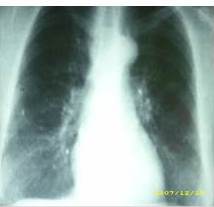

KFK: 100 % Pulso: 78 pm Respiraciones: 19 pm. Femenina que luce en buenas condiciones generales, Piel: sin lesiones evidentes. Cuello: móvil simétrico, no adenopatías cervicales. Tórax: simétrico, normo-expansible, ruidos respiratorios presentes sin agregados, ruidos cardiacos rítmicos normo-fonéticos sin soplos. Mamas: péndulas, simétricas no nódulos palpables, complejo areola pezón sin lesiones. Axilas y fosas supraclaviculares: sin lesiones. Abdomen: blando, depresible, ruidos hidroaéreos presentes. Área inguinal: sin adenopatías. Ginecológico: a nivel de vulva en labios menores se evidencia área eritematosa, igualmente se observa lesión exofítica friable que ocupa 2/3 superiores de canal vaginal y que está firmemente adherida a pared anterior de la misma, esta lesión no permite la visualización del cuello uterino.

Se solicitan estudios de extensión: tomografía axial computarizada de abdomen y pelvis 15/07/2008: no demuestra imágenes de tipo MT a nivel hepático. No se demostraron adenopatías. Aparente aumento de volumen del cuello uterino en relación al cuerpo uterino que es relativamente pequeño. No se puede evaluar con definición el recto por encontrarse muy distendido al momento del estudio (Figura 3).